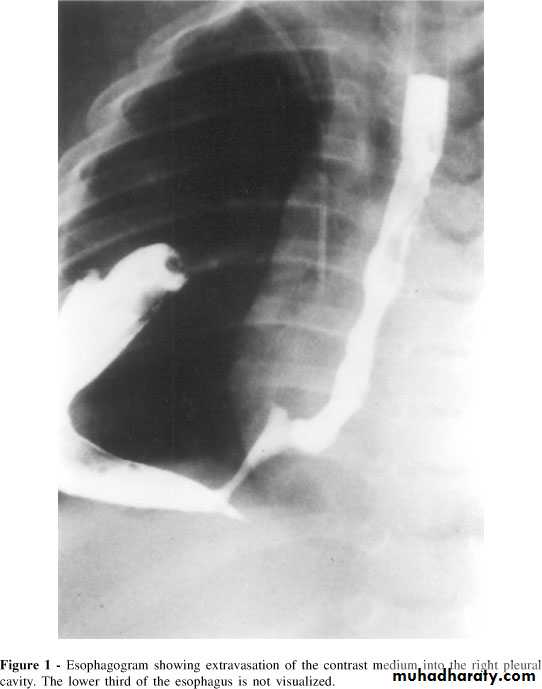

Clinical features Progressive, painless dysphagia for solid foods.In late stages weight loss is often extreme.Chest pain or hoarseness suggests mediastinal invasion.Fistulation between the esophagus and the trachea or bronchial tree; pneumonia and pleural effusion. Metastatic spread is common.

Investigations Endoscopy; The investigation of choice, with cytology and biopsy.Barium swallow ; site and length of the stricture .Thoracic and abdominal CT Endoscopic ultrasound (EUS)